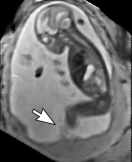

Reconstruction of Fetal Organs: Exemplary PVR and SVR reconstructions under motion introduced by kicking of the fetus are shown in Fig. 11. PVR reconstruction results show an improved visual appearance and less blurring in the region with severe motion artifacts (arrow). An example of a challenging clinical case with a kidney malformation in one of twin fetuses, is shown in Fig. 8. Our clinical partners confirmed that such complications are easier to examine and to quantify after PVR-based reconstruction.

(a) Input

(b) SVR

(c) PVR